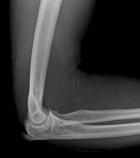

HPI: 80 year old man w/ h/o tumor removed from right forearm in 2002, 2006, and 2008 now states "since last surgery, one bump stayed and one bump went away"

Zoom image: Radiological image Radiological image.